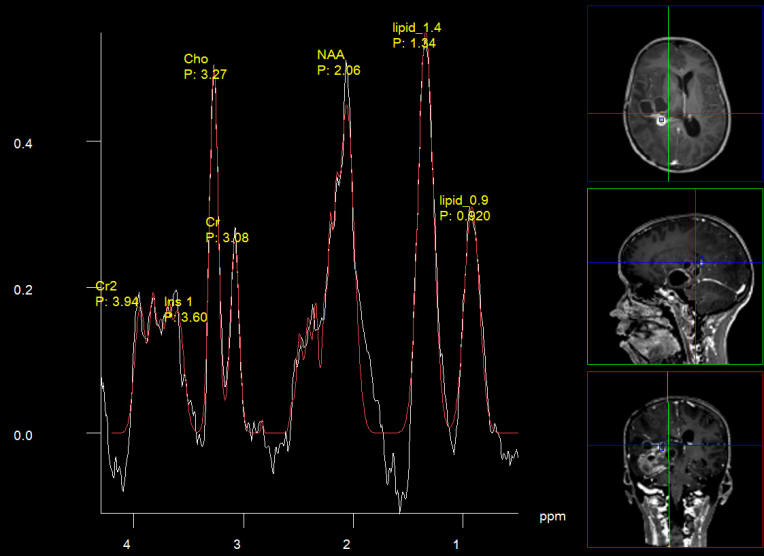

The patient was sent for new MRI of the brain with contrast with MRA of the brain and spectoscopy, DTI and functional MRI and done the same day. The results of investigations shown in Fig. 1-6, listed below.

Figure-1: Choline still high in some places confirming the recurrence of the tumor.

Figure-2: Short TE  showing also the presence of lipids 13 and 9.

Figure-7: Intraoperative spectroscopy showing remnant of active lesion below the cystic lesions, which are abutting the internal capsule. During surgery we use saline and the air come to fill the cavities and an error message coming out during spectroscopy telling that fluid suppression is an adequate. Despite this fact it is possible to catch the active remnants and establish the fluid content of the cysts.